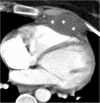

The pericardium could be involved in a variety of clinical disorders. The imaging findings are not specific for an individual pathology in most of the cases; however, patient's clinical history may guide radiologist to a definitive diagnosis. Congenital absence of the pericardium could be recognized with the imaging appearance of interposed lung tissue between the main pulmonary artery and aorta. Pericardial effusion is a non-specific condition that may occur due to inflammatory, infectious, and neoplastic disorders. Cardiac tamponade may occur in case of massive or rapid accumulation of fluid in the pericardial sac. Pericardial calcification is a common and easily identified entity on a computed tomography (CT) scan. Presence of calcification and/or fibrosis may result in pericardial constriction. Nevertheless, the pulsation of an adjacent coronary artery may prevent calcification formation in a focal area and consequently may result in pericardial diverticulum containing epicardial fat and coronary artery. The imaging findings encountered in patients with pericardial hydatid disease and Erdheim-Chester disease may mimic those of pericardial neoplasia. Pericardial adhesions and pedicled fat flaps may cause confusion on a CT scan in the post-surgical period following cardiac surgery. Pericardial fat necrosis can be diagnosed by CT in patients with chest pain. The radiologists should be familiar with the medical devices placed in pericardial space for certain individual indications. A pericardial patch and temporary epicardial pacemaker wires could be identified on a CT scan.